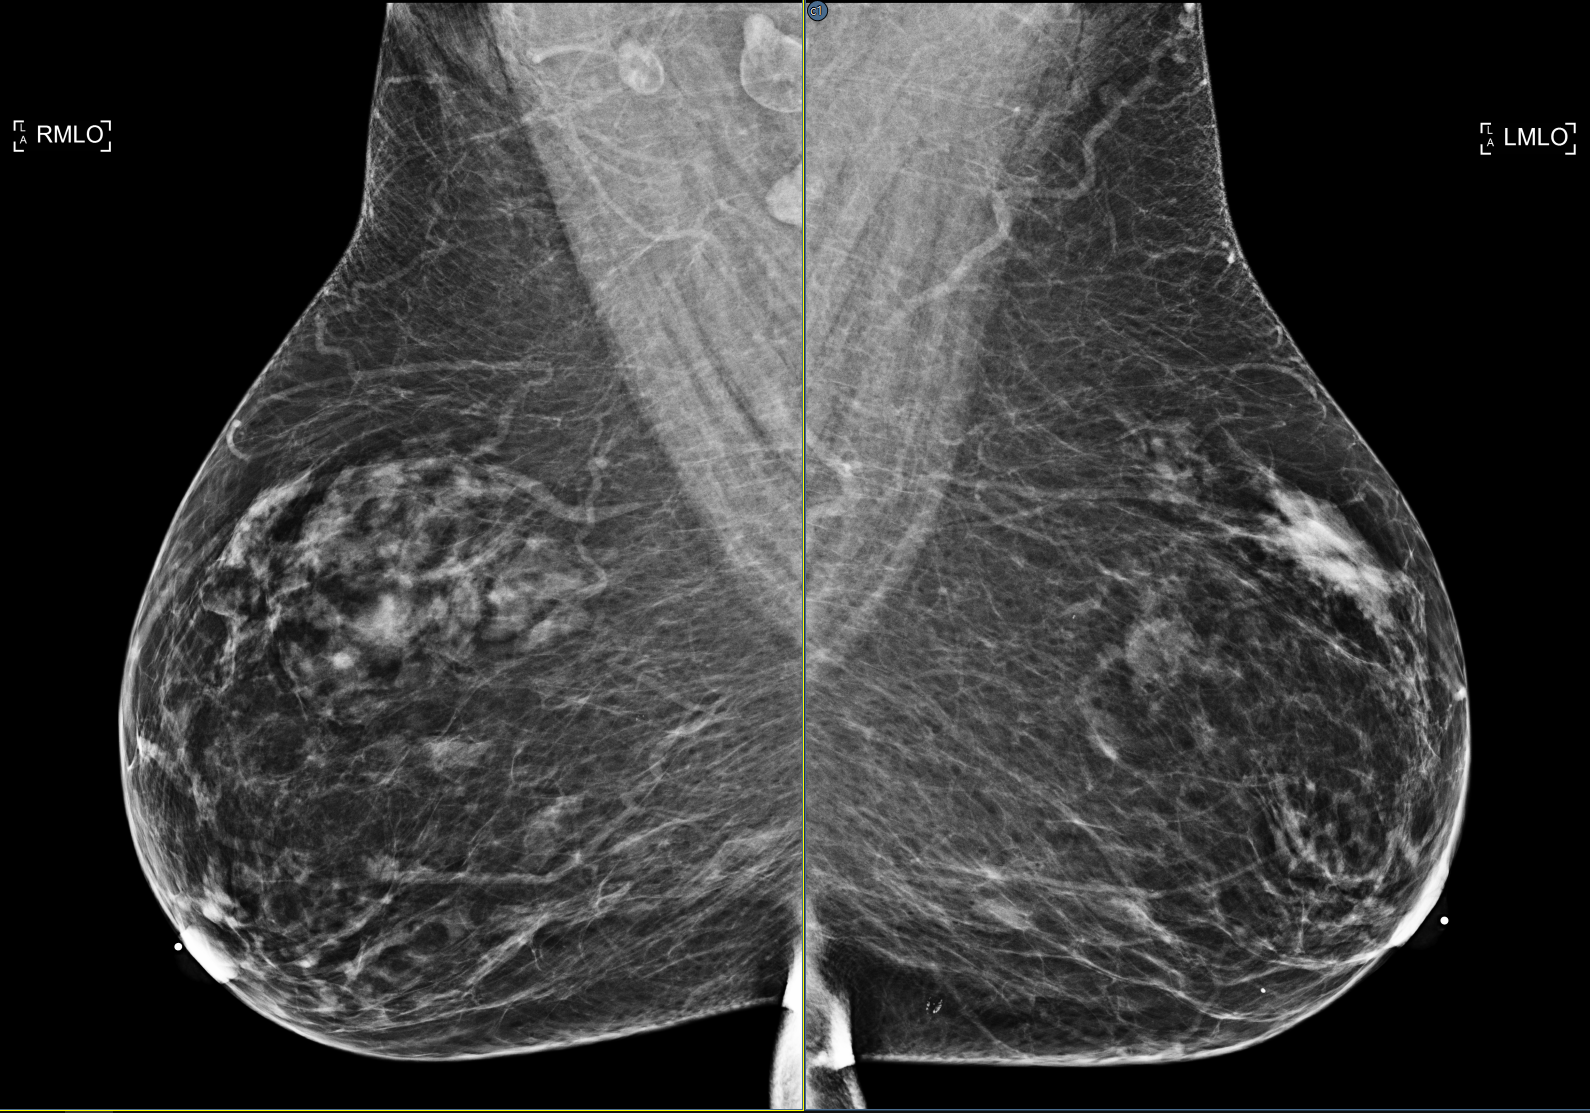

Okos igazítás mód használata esetén, amikor az előmenetel egy mammográfiás képet tartalmazó képkockán jelenik meg, minden lépés automatikusan igazítja a mellkasfalat a képkocka keretének szélén.

A miniatűr panel helymegtakarításához a nézegető az azonos nézetű sorozatokat egy csoportba rendezi. A csoportosított miniatűröket Csoport ikon jelzi a miniatűrképen. A csoportosítási szabályok modalitás-specifikusak. Jelenleg csak az MG támogatott. Az MG sorozatok a nézet pozíció és az oldalirányúság szerint csoportosíthatók. Csoportosítás esetén az egér bal oldali gombjával kattintson az egyes miniatűr képkockákra a csoport kinyitásához, hogy a csoportban lévő minden egyes sorozat összes miniatűrképe látható legyen. Kattintson duplán a miniatűr képkockára, vagy húzza el a sorozat képkockába való betöltéséhez. Kattintson duplán a csoport miniatűr képkockájára, vagy húzza el, hogy az egész csoportot betöltse egy képkockába. A vizsgálatban lévő összes sorozat csoportbontásához kattintson a jobb gombbal a csoport miniatűr képére, és válassza a felugró menüből a Csoportbontás parancsot. A csoportosítási beállítások testreszabásához aktiválja az Elrendezés szerkesztőt. Ez a jobb klikk menüt konfigurációs eszközökkel egészíti ki.

Ha a mammográfiás sorozat folttömörítésű képeket tartalmaz, az okos igazítás le van tiltva, mivel a képek további jellemzőket, pl. foltokat tartalmaznak, amelyek nem kívánt eredményeket produkálnak.

Egy új beállítás, amely növeli a nézegető SmartFit zoomolási képességét azáltal, hogy azonosítja a nem-mell anatómiát, és kizárja azt a normál Okos igazítás számításokból. A kép pásztázásával az adatok továbbra is elérhetőek maradnak. A beállítás alapértelmezés szerint ki van kapcsolva. A funkciót a nézegető beállítási paneljének Képek/Zoom szakaszában található Feljavított okos igazítás beállítással lehet engedélyezni. Lásd: Képek